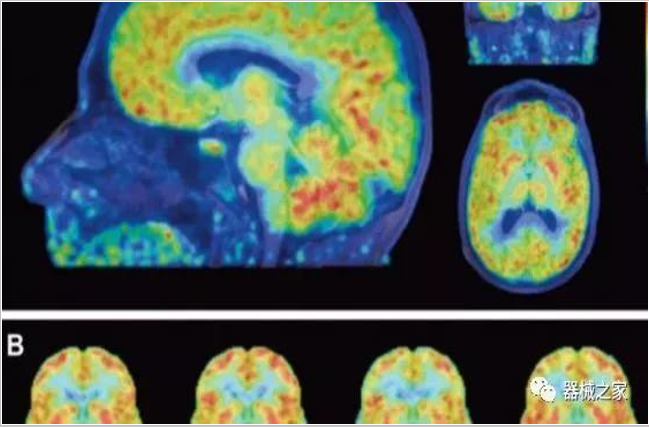

正電子發(fā)射型斷層儀(Positron Emission Tomography, PET)是對正電子示蹤劑的探測設(shè)備,具有極高靈敏度和精準(zhǔn)的定量功能。而PET/CT是將PET與CT有機(jī)結(jié)合起來的融合設(shè)備,已經(jīng)成為腫瘤、神經(jīng)和心血管系統(tǒng)疾病診斷,臨床分期和療效評估的最佳影像技術(shù)。